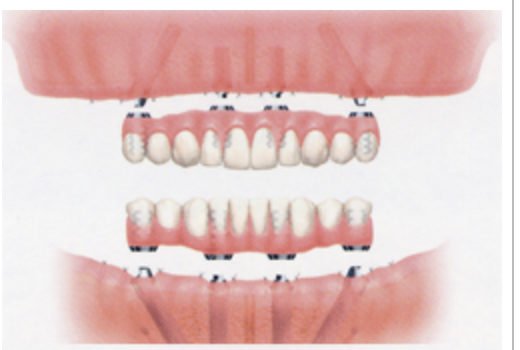

今はこんな感じで、

多くて6本、基本的には4本で十分。なぜなら、インプラントを多く入れれば入れるほど、骨吸収が生じる、メインテナンスの部位が増えて口腔衛生上、プラークコントロールが大変、本数が増えるとそれだけ経済的な負担になるというところが理由です。

そして力学的な負担を少数のインプラントで支えるために、長め、太めのインプラントを使用します。